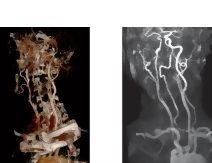

Angiography: Computed Tomography Angiogram Vs. Magnetic Resonance Angiogram and Volume Rendering Vs. Maximum Intensity Projection